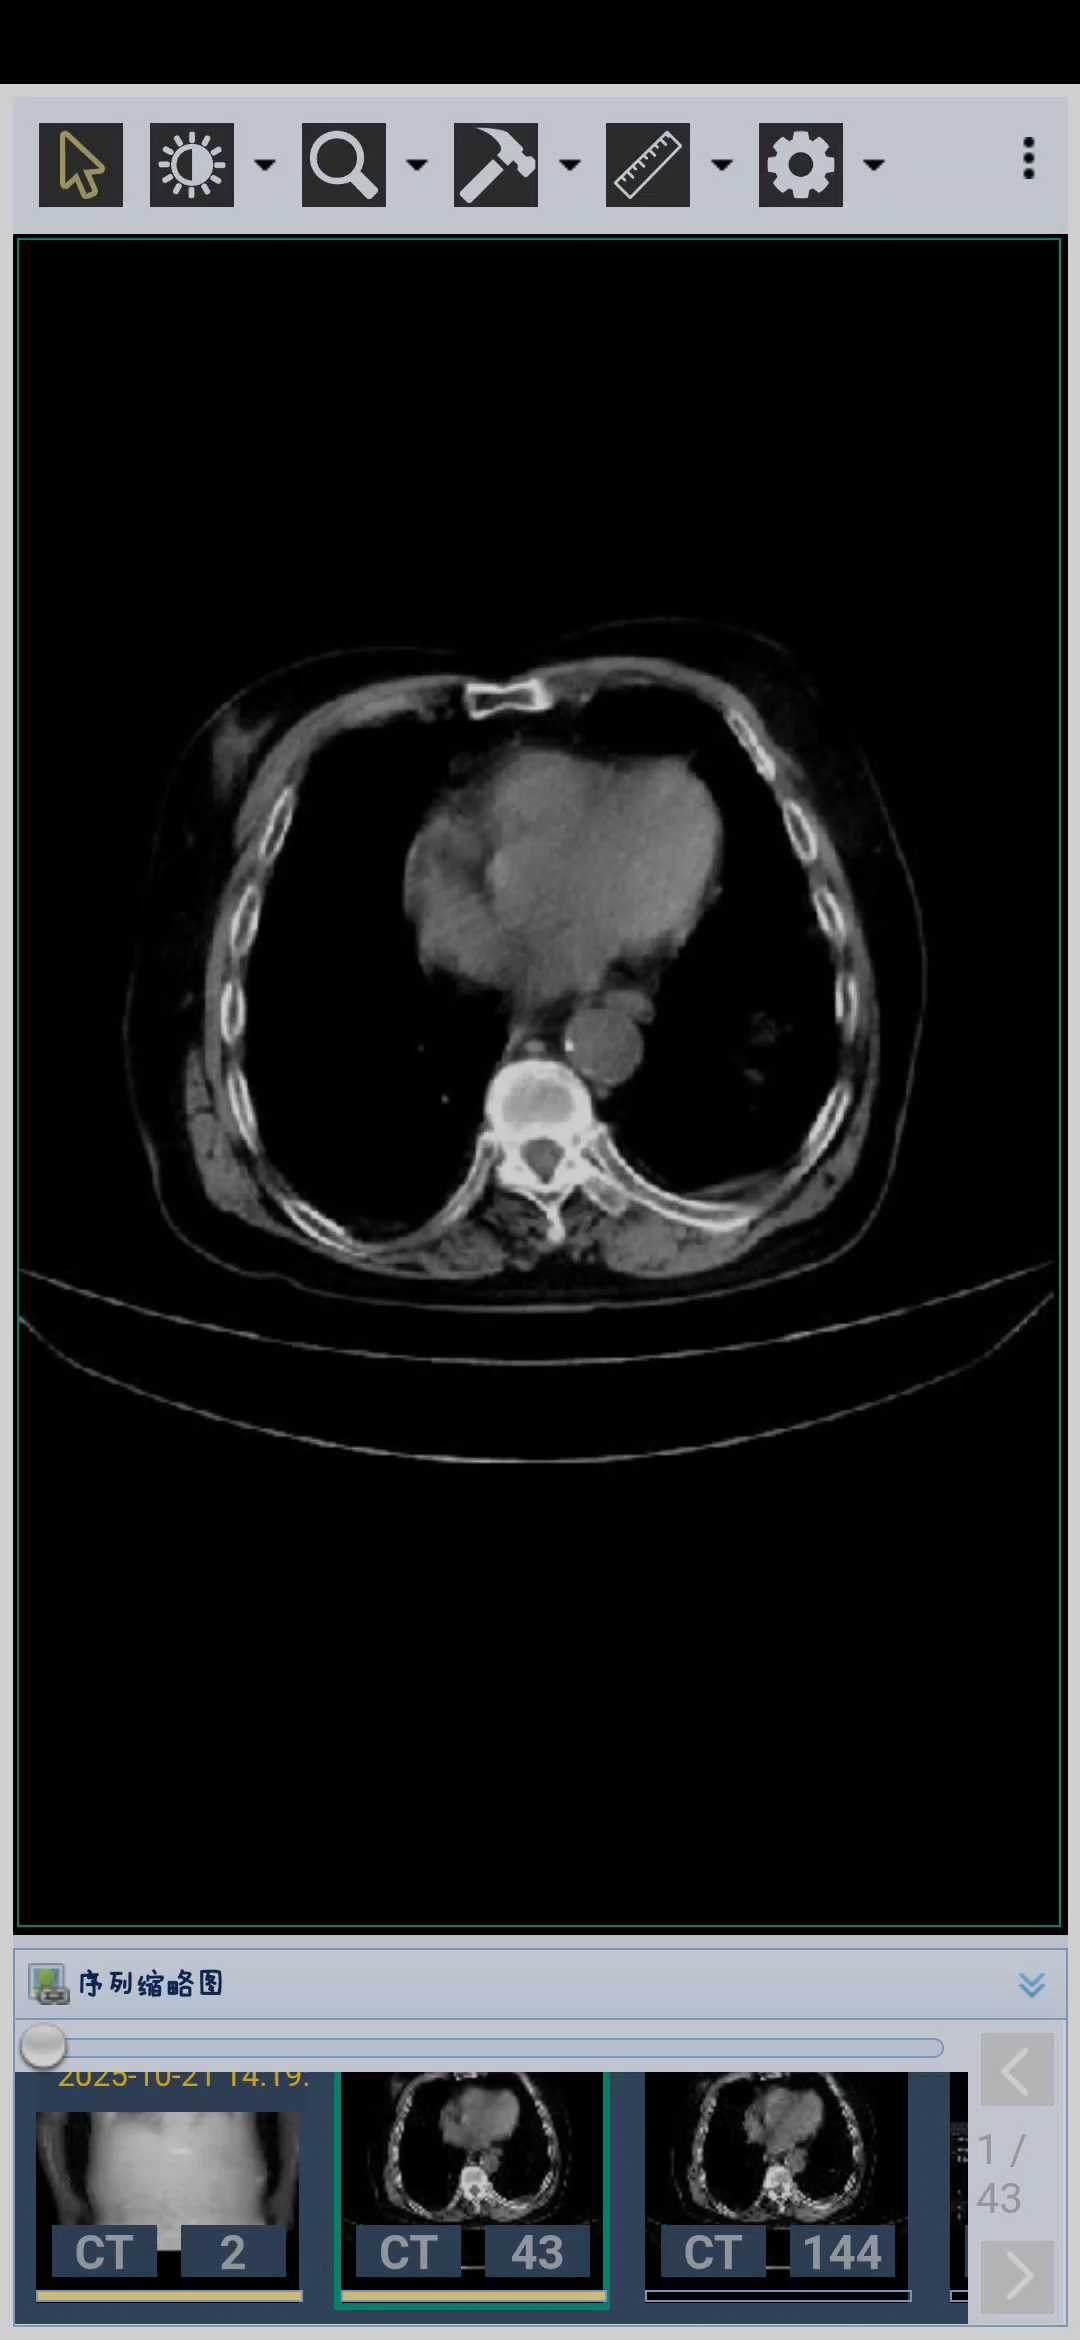

病例85岁老人胆总管扩张的可怕

病例信息